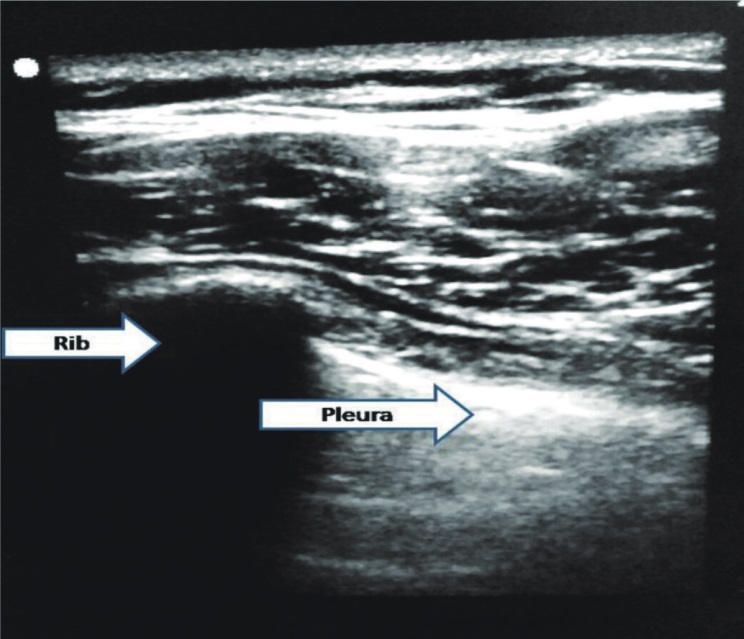

In Group P

(1) Probe placement: Vertically at the second or third intercostal space in the sagittal plane at the midclavicular line (depth 4.7 cm) (Figure 2)

Figure 2.

Download full-size image

Fig. 2. Preprocedural Scan for Pleural Ultrasonography

(2) ETT placement confirmation: By the bilateral lung sliding sign as shown in USG (Figure 4)

Fig. 4. Pleural Ultrasonography Showing Lung Sliding (Rib and Pleura)